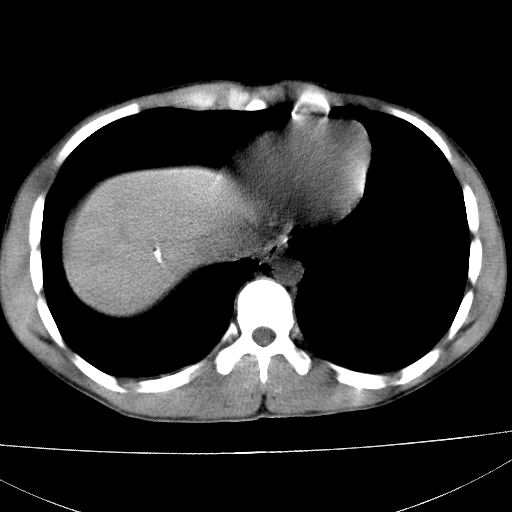

1)肝破裂伴腹腔积液(血)。2)右肾破裂伴右肾包膜下及肾周血肿。3)腹部空腔脏器穿孔可能。4)右侧少量胸腔积液(血)。

1)肝破裂伴腹腔积液(血)。2)右肾破裂伴右肾包膜下及肾周血肿。3)右侧少量胸腔积液(血)。

1)肝破裂伴腹腔积液(血)。2)右肾破裂伴右肾包膜下及肾周血肿。3右侧少量胸腔积液(血)。

肝右肾挫裂伤,右肾包膜下及肾周血肿.胸腹腔少量积液.脾脏下部密度稍不均,必要时,增强.